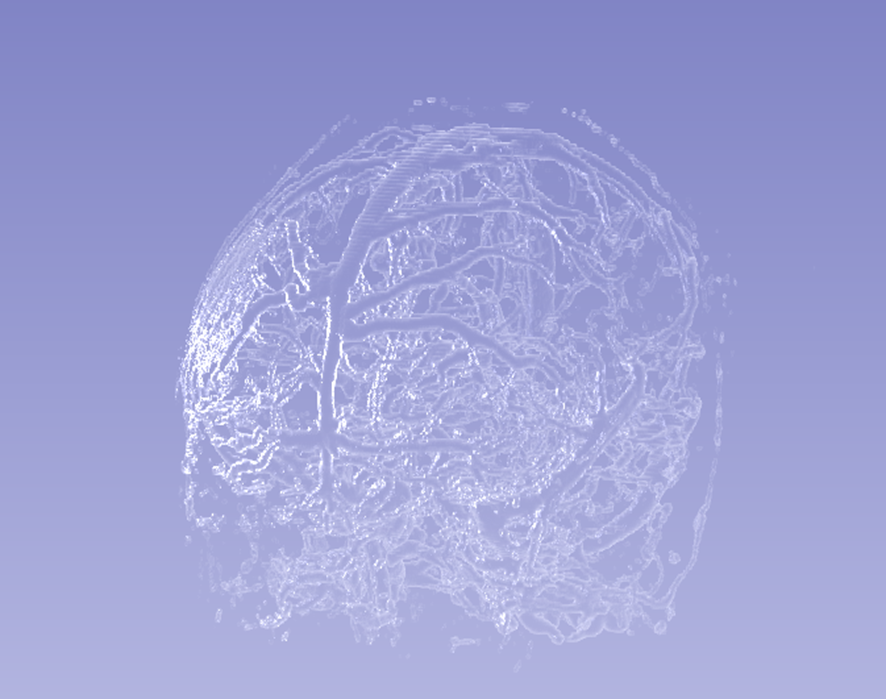

- Develop a new shader or modify the outline shader to be able to produce glass-like rendering of tissue boundaries in a volume

- The glass effect could be obtained by modifying the outline shader to modulate the transparency of the volume by the specular term of the phong model in regions where the volume gradient’s amplitude is high.

- It may be necessary to apply a gaussian filter to the volume before computing the gradient if the signal is too noisy to produce an interesting specular highlight.

- Implemented a first version of the glass volume rendering effect (see illustration below)

Current version of the glass effect